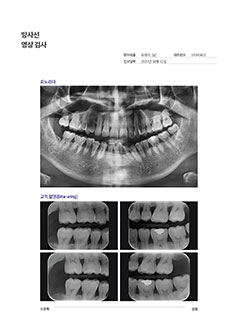

拍摄CT & X光片

Computed Tomography / Panorama

[ 拍摄CBCT ]

牙科CBCT拍摄是利用X线

3D视频重现牙槽骨和牙齿的硬组织 .

[ PANORAMA ]

确认整个牙齿的现状和

排列, 咬合, 颚关节状态 .

可确认牙槽骨吸收, 牙根炎症,

修复体的状态, 牙齿的状态等等 .

Oral Photography / Bite-Wing Radiography / Periapical Radiograph

[ 拍摄口腔内部 ]

从前牙到后牙, 临街牙齿部位,

牙齿平面的蛀牙及治疗状态都能扩大确认 . -

[ 拍摄咬翼 ]

为了更仔细确认牙齿头部拍摄X光片,

有效预防不能早期发现的牙齿面蛀牙 . -

[ 拍摄牙根 ]

* 需要时拍摄为了更仔细, 精密的检查问题牙齿拍摄X光片,

牙根底部炎症, 牙齿根管状态, 一般蛀牙等2次蛀牙都能确认 .